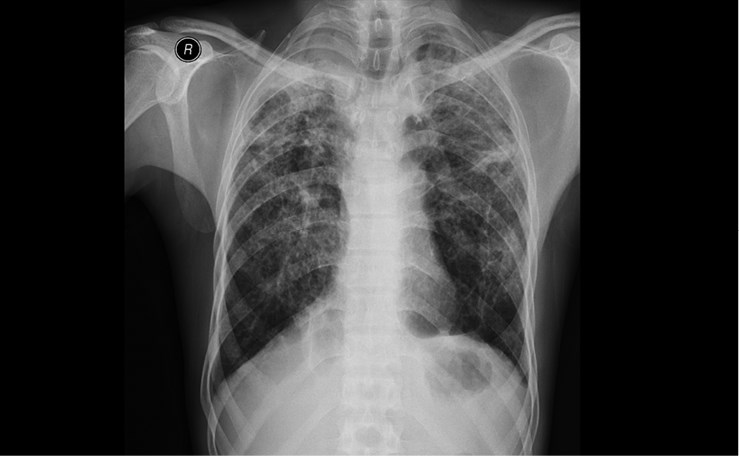

2. Рентгеновский снимок груди одного из молодых людей, занимавшихся пескоструйной обработкой джинсов с 2000 по 2003 г. У них был диагностирован силикоз (осложненный) в 2011 г. Белые зоны на снимке демонстрируют тяжесть заболевания. Изображение любезно предоставлено доктором Метином Акгуном, Университет Аттатюрка

Деним стал одной из самых популярных тканей в мире. Так как его носят мужчины, женщины и дети, деним можно считать повседневной униформой XXI века. В городе Ксинтанг (Китай), джинсовой столице мира, сточные воды после производства двухсот миллионов пар джинсовых брюк, отшиваемых там ежегодно, окрашивают Жемчужную реку в темно-синий и даже черный цвет[627]. Сложный химический коктейль попадает в воду каждый раз, когда появляется новая пара джинсов. Кроме того, начиная с 1970-х годов многие из этих только что выкрашенных синих джинсовых брюк подвергались дополнительной токсичной обработке для придания им состаренного вида. Производители удаляют краситель пятнами или полосами, чтобы создать декоративные «уникальные» следы износа и изобразить патину времени. Техники такого окрашивания включают ручную обработку наждачной бумагой и отбеливание, что вызывает у работников астму. В 1990-х годах была разработана новая технология пескоструйной обработки для «изнашивания» джинсовой ткани, которая в свою очередь изнашивала организмы сотен, а может, и тысяч турецких мужчин. Они работали на установках, обдувающих джинсы абразивным кремнийсодержащим песком, который оставил в их легких неизлечимые шрамы (ил. 2). Турецкие врачи были обескуражены, когда в 2004 году двое подростков погибли от силикоза. Это заболевание распространено у шахтеров и камнеломов и хорошо известно медикам. Но в швейной промышленности эта угроза здоровью рабочих возникла впервые[628]. Специалисты в области профессиональных заболеваний обследовали и опросили мужчин, по 10-12 часов в день 6-7 дней в неделю обрабатывавших деним пескоструйным аппаратом в тесных плохо проветриваемых мастерских Стамбула. Зачастую рабочие и ночевали в том же помещении за занавеской. Мало кому из них достались защитные маски с респираторами, и половина рабочих, участвовавших в обследовании, страдали силикозом[629]. Почти никто из них не получил компенсации. Турецкое правительство запретило эту технологию в 2009 году, но с тех пор ее стали использовать в менее развитых странах с более низким уровнем контроля. Как и другие предметы одежды, описанные в этой книге, многие пары джинсовых брюк все еще хранят на себе как отметины производственного процесса, который их «состаривает», так и уникальный рисунок травм, который эта работа оставила на легких их производителей[630].